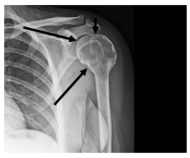

A imagem apresenta uma radiografia do ombro esquerdo do paciente.

Fonte: Guilherme Pioli Resende et http://bradcasesold.brad.org.br/pt/Cases/CaseDetails/232 al (2021).

A região assinalada na imagem é denominada: